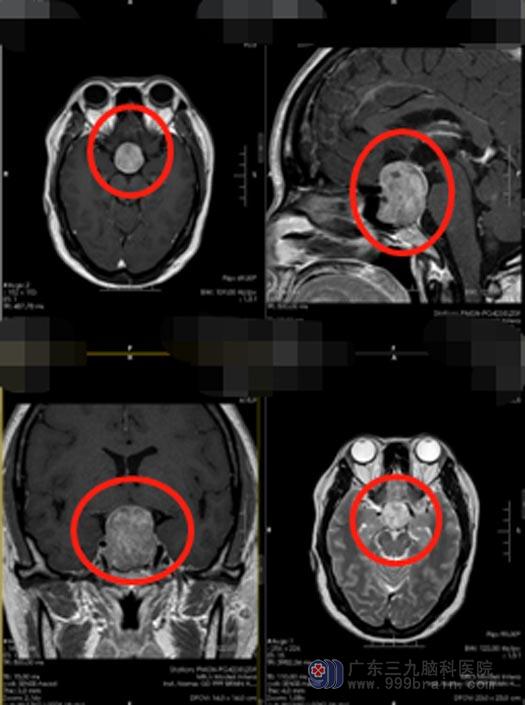

3个月前,雷女士发现自己的视力下降得更加明显,右眼仅仅只有光感,并伴有头痛、头晕。她觉得这明显是不正常了,在家人的陪同下去了眼科医院,医生检查后,没有发现雷女士的眼睛有异常,建议去检查脑部,头颅CT+MRI检查结果:考虑鞍区占位,垂体瘤可能。

垂体瘤是良性肿瘤,是颅脑中一个非常特殊的肿瘤,不同的垂体瘤,表现的症状也不一样。垂体肿瘤如果向鞍上生长,突入鞍上池,压迫到视神经传导物,能使得患者视物范围变小,颞侧、鼻侧视野缺损,表现为进行性视力下降、突然头痛并视力下降;一般1-3cm的大腺瘤或大于3cm的巨大腺瘤,都会引起不同程度的视力问题。手术切除是治疗的首选。

为了更好地进行治疗,广东三九脑科医院副院长、神经外五科主任鲁明带领团队对患者的具体病情进行了讨论,大家一致认为,雷女士已经出现了视物模糊、头痛及恶心等情况,手术指征明显,应及早手术,否则患者的这些症状还会加重,视力会越来越差直至失明。